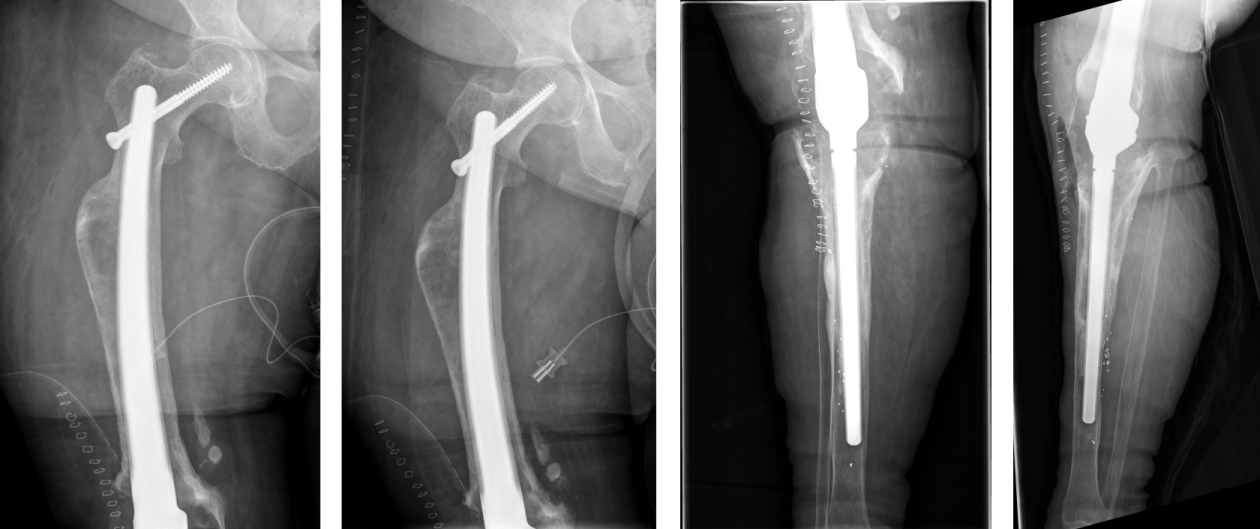

The duration of the surgical intervention was four hours and eight minutes. The patient was then mobilized with full weight bearing supervised by physiotherapists at ward level, which she tolerated well. The pain was significantly relieved during the hospital stay. The postoperative radiographs showed correct implant position and a satisfactory surgical result (Figure 9 [Fig. 9]). Microbiological and histological samples obtained intraoperatively showed no evidence of infection. Yet, the patient presented postoperatively with complete loss of active dorsiflexion of the ipsilateral foot. Neurological consultation and investigation confirmed the diagnosis of peroneal lesion. The patient was supplied by orthopedic shoes and orthesis. Further, electrotherapy was carried out.

Figure 9: The postoperative radiographs showed correct implant position and a satisfactory surgical result.

On one-year follow-up, the patient did not complain of any pain. The radiological findings one year after surgery showed no sign of loosening or any other pathological findings (Figure 10 [Fig. 10]). The neurological lesion has completely recovered. The Harris Hip Score HHS improved from 24 (prior to implantation of the arthrodesis) to 75 on one-year follow-up, the Western Ontario and McMaster Universities Osteoarthritis Index WOMAC improved from 86 to 20. The range of motion of the right hip joint one year after surgery was: extension/flexion 0/0/100°, abduction/adduction 30/0/20°, external rotation/internal rotation 30/0/20°.

Figure 10: The radiological findings one year after surgery show no sign of loosening or any other pathological findings.